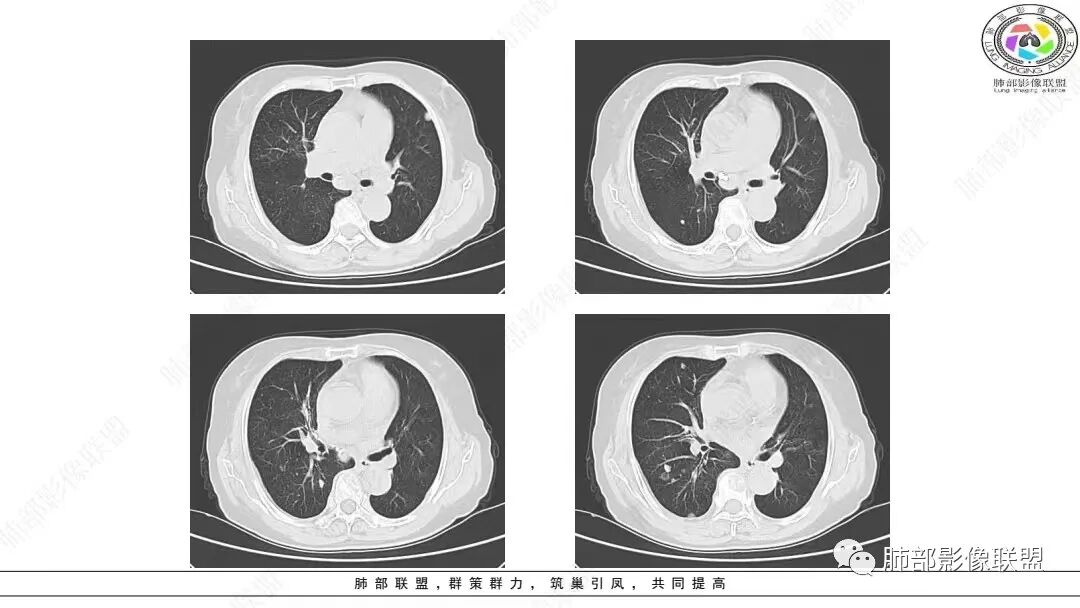

2.影像学特点:右肺上叶前段胸膜下不规则较大团块影,边界清楚欠光整,浅分叶,肺血管支气管出入,边缘膨隆胸膜凹陷具有一定张力,未见典型粗短毛刺,部分围以边界清楚的磨玻璃影,灶周小叶间隔增厚。块影密度不均,渐进性强化,可见砂砾样钙化,未见明显液化坏死或空洞。增强后病灶显示渐进性强化。MIP显示病灶内肺动脉穿行、并部分肺动脉受侵变细。纵隔及右锁骨上(胸廓入口)见肿大淋巴结。两肺可见多发大小不一的结节影,边界清楚,随机分布。

病灶较大较光整,支气管出入,缀以边界清楚磨玻璃影,有一定张力,不均匀强化,疑及肺腺癌或者大细胞肺癌都在情理之中。双肺多发病灶,符合转移瘤特征。     注意胸椎体溶骨性吸收破坏,突破骨皮质,经验上这样的改变更支持转移而不支持淋巴类肿瘤。

本组50.82%(124/244)病灶周围见磨玻璃密度影改变,33.20%在磨玻璃密度影中伴有小叶间隔的间质增厚,表现为小叶间隔网格状增粗,但不伴有串珠状排列的小结节;其形成机制可能是肿瘤周围实质及间质均伴有大量淋巴细胞浸润以及小叶间隔的淋巴管扩张,而肺腺癌或鳞癌的癌性淋巴管炎多表现为小叶间隔结节状增厚,可呈串珠状改变。上述征象可作为肺LELC与肺鳞、腺癌的鉴别点。

综上所述,右肺中叶、两肺下叶纵隔胸膜旁肿块,边界清、浅分叶、淋巴结肿大,伴有类胸膜尾征、增强动脉期血管包埋征、周围肺区磨玻璃密度影及网格增粗影是肺LELC相对特征的CT表现,但最终诊断仍须依赖组织病理学和免疫组织化学染色结果。